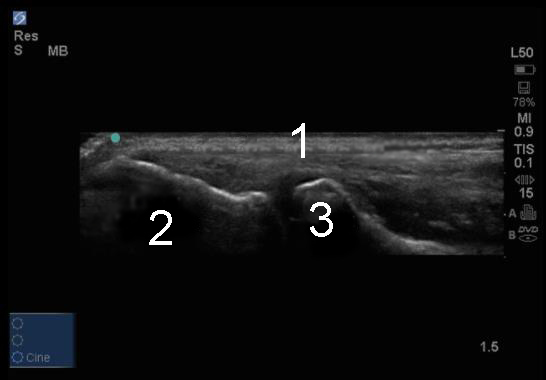

Elbow Common Extensor Tendon Image

Common Extensor Tendon

Lateral Epicondyle

Radial Head